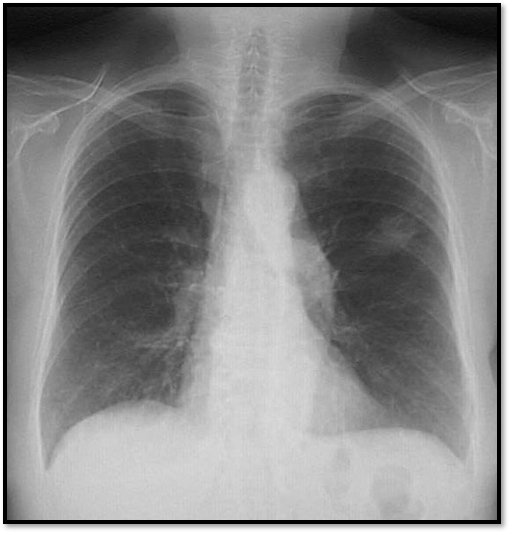

List 3 causes for the condition shown in the attached image

What’s your diagnosis?

List the 3 most common conditions responsible for this appearance.

Cannon ball metastases

Commonest primary sites: Breast > colon>renal